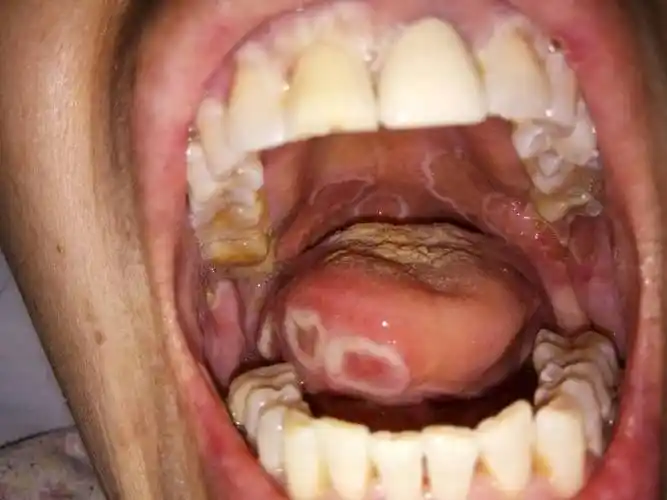

新乡市老中医看烂嘴图片经验分享,口腔溃疡就是烂嘴,口腔是消化的第一

口腔溃疡

口腔溃疡竟会癌变?看看你是良性还是恶性

这是什么类型的口腔溃疡?

口腔溃疡若长在这区域要警惕癌变